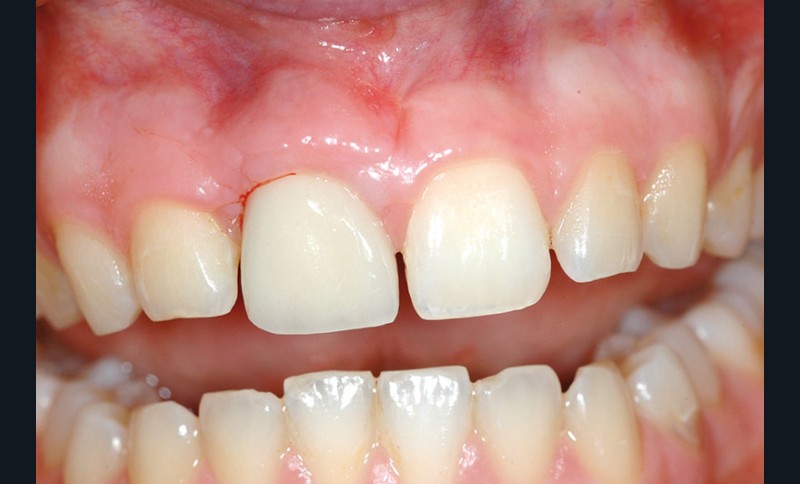

Nous proposons de retirer la couronne et le pilier implantaire, d’effectuer une greffe de tissu conjonctif enfouie afin d’améliorer le volume du tissu kératinisé péri-implantaire [5] et de procéder à la pose d’une couronne provisoire transvissée (fig. 3a à h).